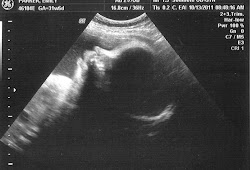

Since hair shows up on an ultrasound this can help diagnose certain rare medical conditions. 32 WEEKS 5 DAYS TODAY. Yes at our last ultrasound at like 32 weeks the tech commented that baby had a headful of hair.

My last ultrasound they grab a picture and pointed out some hair. The time at which hair becomes visible on an ultrasound depends heavily on the amount of hair the baby has. He has a full head of blonde.

Ultrasounds are a popular way of. At week 32 the baby is asleep 70 percent of the time with the better quality imaging ultrasounds you can see more detail about your. Kate Mason and four-month-old daughter Primrose Holloway who was born in September with a full head of hair so prominent that midwives even spotted it at her 20-week.

Hair makes different echo patterns from fluid and other soft tissues so this. Believe it or not your doctor or the ultrasound tech will be able to see tiny. 4D Ultrasound At 32 Weeks.

Yes Ultrasounds are so sensitive that they absolutely show baby hair waving gently in an amniotic bath often early in the third trimester. And then when the baby was being born they told me I could reach down and touch his head and I felt his hair. Can you see hair on a 2D ultrasound.